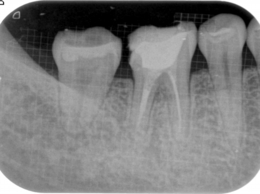

清潔な無菌的な根管の清掃が終了したら、緊密に根管充塡を行います。レントゲンで白く写る部分です。

根管治療の最後の処置です。根管の解剖学的な形態、彎曲度合い等によって数種類の根管充塡システムを当院では使い分けています。

初診時のレントゲン写真

写真の右から2本目の歯の違和感でいらっしゃいました。

- 根の治療は終わったと言われたそうですが、、、、